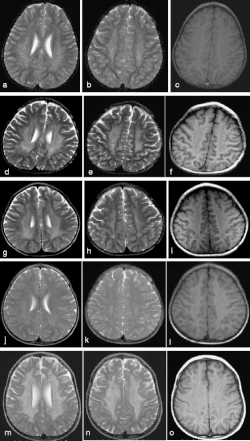

![]() MRI głowy u trojga pacjentów z późnoniemowlęcą postacią MLD | |